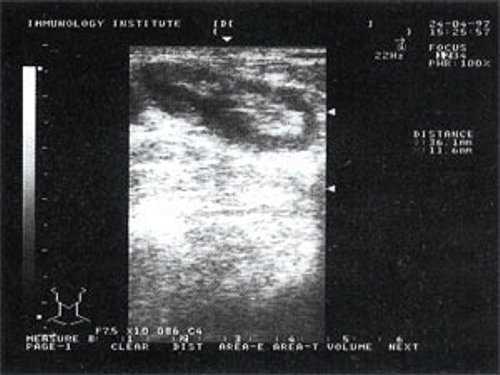

Мы выявили совершенно другую УЗ-картину состояния пальпируемых лимфатических узлов при динамической оценке у больных с синдромом иммунодефицита. Оцениваемые лимфатические узлы имели эхографические признаки доброкачественного процесса, в большинстве наблюдений их размеры превышали 2-2,5 см. При этом во всех случаях дифференцировались составные части лимфатического узла. Определялся узкий кортикальный слой и широкая гиперэхогенная сердцевина при сохранении овальной конфигурации и соотношении поперечного/переднезаднего более 1.

При повторных УЗ осмотрах на фоне массированной противовоспатительной терапии было отмечено увеличение числа лимфатических узлов вовлеченных в процесс активизации. При этом заметной перестройки эхоструктуры и уменьшения размеров в наблюдаемых лимфатических узлах отмечено не было (рис 4).

![Изображение увеличенного лимфатического узла с УЗ-признаками доброкачественной аденопатии у больного с синдромом иммунодефицита (а)]()

![Изображение увеличенного лимфатического узла с УЗ-признаками доброкачественной аденопатии у больного с синдромом иммунодефицита (б)]()

Рис. 4. Варианты изображения увеличенного лимфатического узла с УЗ-признаками доброкачественной аденопатии у больного с синдромом иммунодефицита.